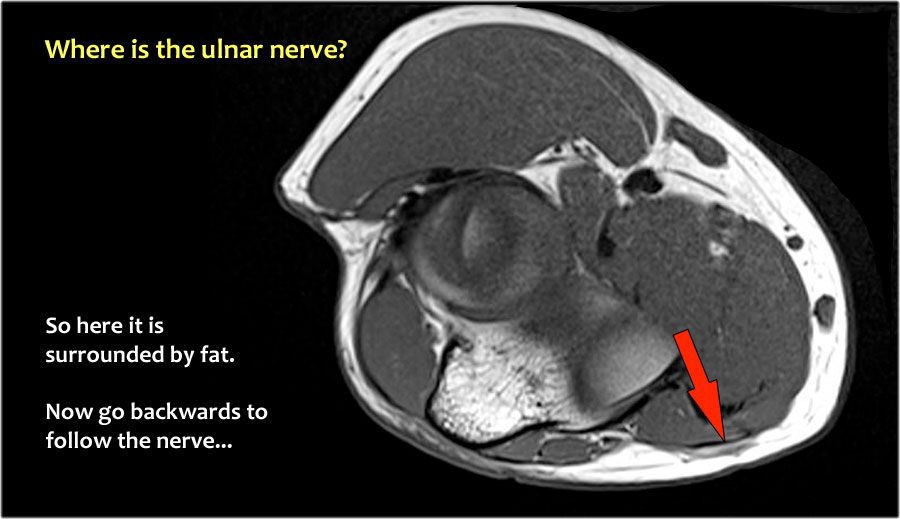

Một cách để thực hiện là đi theo các cấu trúc về phía xa cho đến khi tìm thấy dây thần kinh trụ ở phía xa tại vị trí bình thường của nó ở vùng cẳng tay gần được bao quanh bởi mô mỡ.

Sau đó khi bạn theo dõi nó về phía gần, bạn sẽ nhận thấy rằng đây là một trường hợp chuyển vị dưới da.